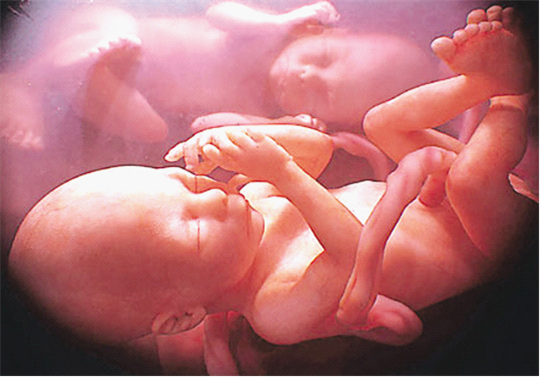

医 学杂志上对多胞胎的解释是:当女性每个月产卵数多余一个并且都能成功受精,或是一个受精卵分裂为多个,这两种情况下都有可能产生多胞胎。随着体外受精技术 的发展,多胞胎在现代社会越来越会常见。所谓的体外受精也就是向受孕者的子宫里输入多个受精卵,只要有一个存活下来,便能生出健康的婴儿。如果多个受精卵 多成功存活,那就能产生多胞胎。

但是,一个女人的子宫最多能容纳多少个婴儿呢?大多数人可能会觉得六胞胎已经很不可思议了,但事实上,六胞胎发生的几率并不低,甚至七胞胎也有真实案例可以证明。